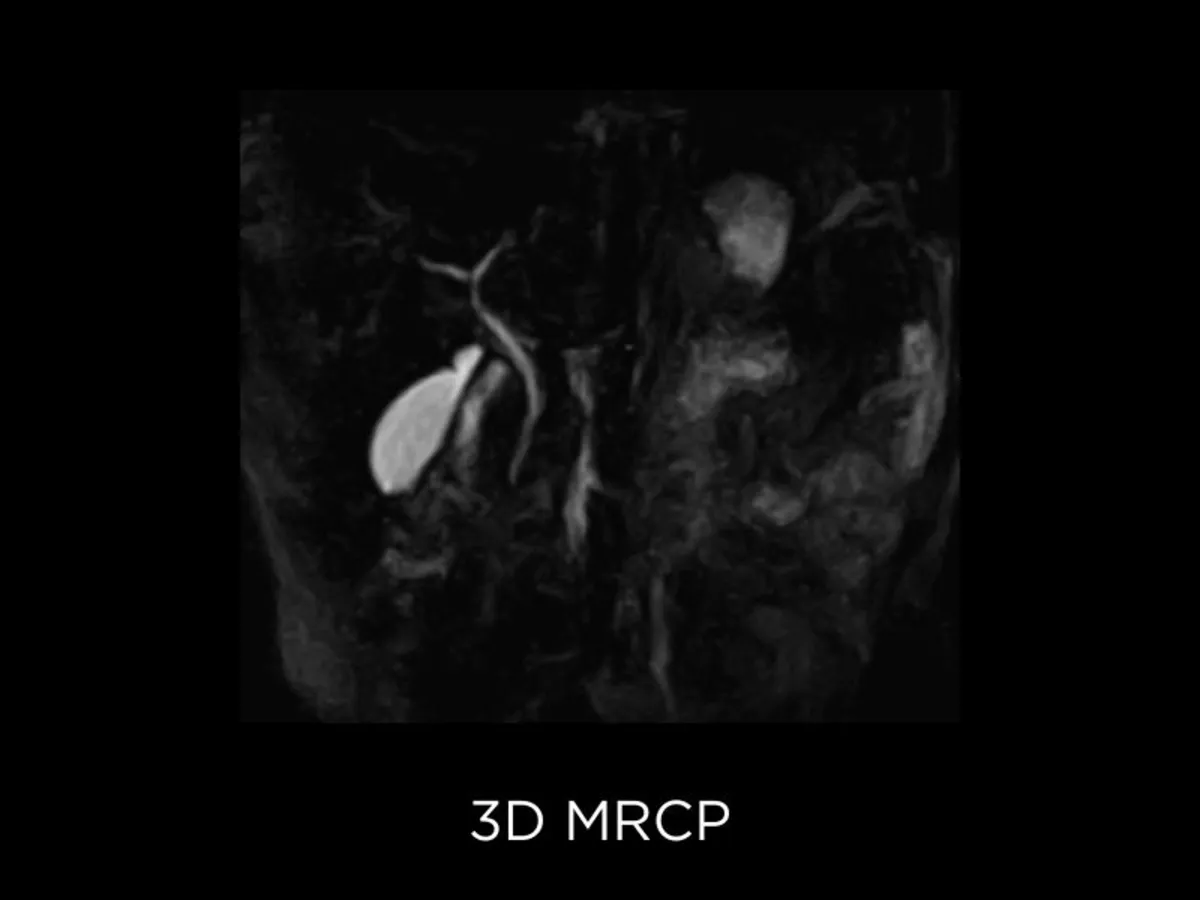

TOF sequences

Time of Flight angiography (TOF) is aimed at visualizing flow within vessels, even without contrast injection (MRA). 2D TOF is more sensitive to slow flow and it is more useful to assess long vessels whilst 3D TOF usually is preferred in the study of tortuous vessels (I.e. Circle of Willis)3. These sequences are crucial in the assessment of several conditions such as intracranial aneurysm and vascular stenosis.

The Time-Of-Flight (TOF) effect in MRI arises due to the blood flow between the RF pulses. The TOF effects in gradient-echo imaging appear as a signal hyperintensity due to the in-flow of fresh blood that has not experienced any prior RF pulses. Nonetheless, Esaote implemented innovative techniques to increase the image resolution and decrease sensitivity to the effects of flow saturation. The User Interface also includes Maximum Intensity Projection (MIP) software to proficiently reconstruct MR Angiograms detail vascular area of interest.

• FSE 3D: provides high SNR and contrast for thin-slice MRCP imaging.

Abdominal imaging clinical images